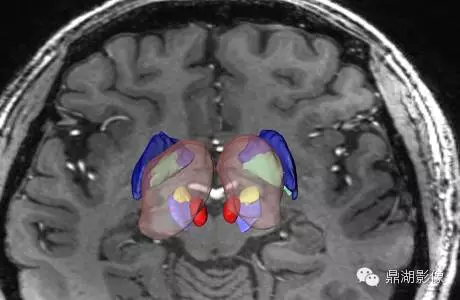

这是一个例对灵长类动物的分子影像学研究

4.Scientific Session 13: Central Nervous System

September 9, 2011:PET/CT/MRI with [18F]TFAHA using an optimized pharmacokinetic model for quantification of HDAC class II expression-activity in the brain in non-human primates